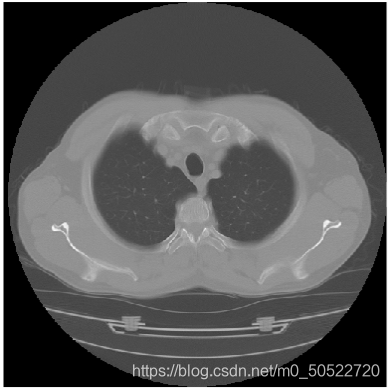

(1)dicom文件的读取

dicom是委员会开发的用于成像设备之间进行通信的标准。使用dicomread函数读取dicom文件,并显示原始横截面胸部 HRCT 层片。